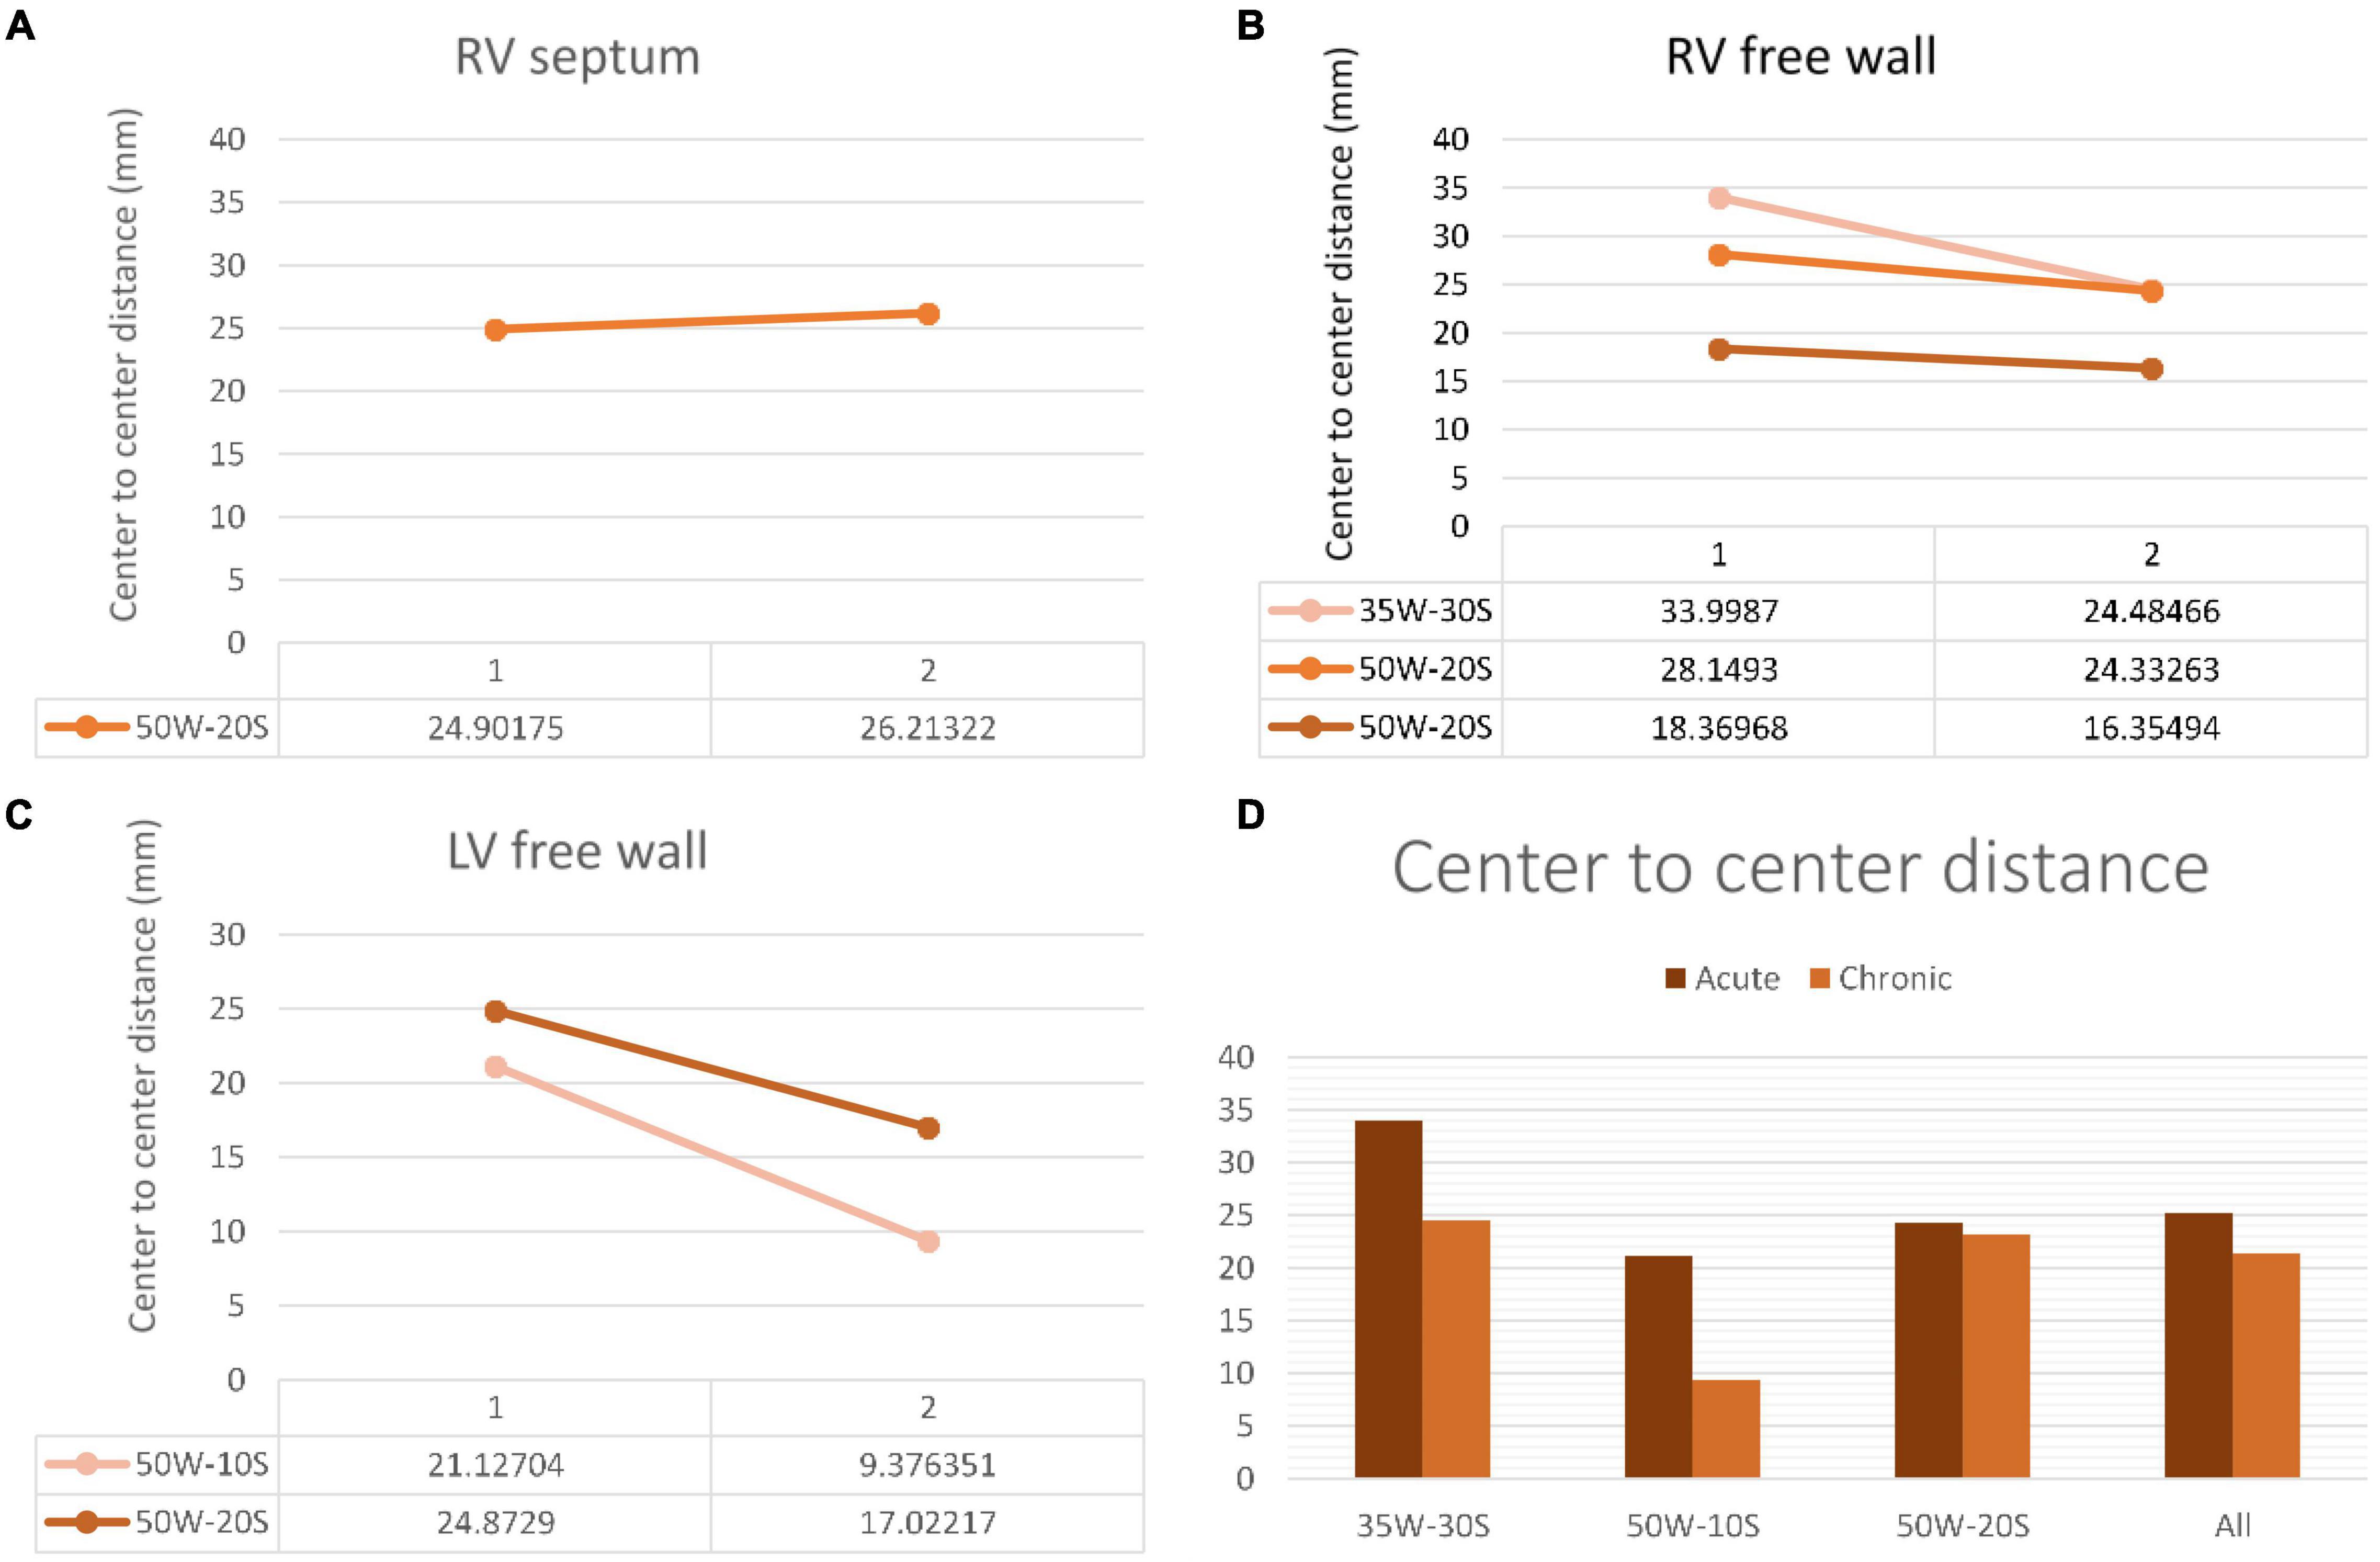

d- Distances Measured on LGE-MRI in Unconnected Lesions:

The average center-to-center distance between unconnected lesions as quantified by LGE-MRI was 24.27 ± 1.60 mm and 23.15 ± 2.91 mm at the acute and chronic stages, respectively. In addition, the edge-to-edge distance between these paired lesions as quantified by LGE-MRI at the acute and chronic stages were 4.35 ± 1.27 mm and 4.15 ± 0.95 mm, respectively. Center-to-center and edge-to-edge distances were reported on a limited number of paired lesions where clear lesion contours allowed calculation of such distances: Therefore, performing statistical analyses on these corresponding pairs was not possible due to the very limited number of pairs. No p-values were calculated.

Edge to edge distance and center-to-center distances are shown in Figures 6, 7, respectively. According to our findings, lesions created in RV free wall and septum have little to no reduction in center-to-center distance. Instead, they demonstrate a small decrease in their edge-to-edge distance. However, lesions created in the LV tended to have a larger reduction in center-to-center distance with no change in their edge-to edge-distance.

Figure 6. Center-to-center distance progression at varying doses and regions within the heart determined by MRI. The variation in center-to-center distance between the acute and chronic settings is shown in the RV septum (A), RV free wall (B) and LV free wall (C). Overall average of acute and chronic center-to-center distance between lesions created at varying ablation parameters (D). Every line in each graph represents the variation of center-to-center distance between one pair of ablation points (50W-20S are shown twice as two pairs were created using this parameter). For instance, in the LV free wall, the center-to-center distance reduced from 21 to 9.3 mm from the acute to chronic settings in a pair of lesions. Another pair reduced from 24.9 to 17 mm.

Lesion Size Regression

Our investigation is the first to study lesion evolution by looking at center-to-center and edge-to-edge distances. In the septum and RV free wall, edge-to-edge distances became smaller with time, but center-to-center distances stayed relatively constant. This can be explained by the time dependent resolution of edema and shrinkage of the lesion. However, in the LV free wall, even center-to-center distance became smaller. This suggests a greater degree of edema in the LV free wall compared to other locations. A possible explanation to this finding is that higher strain and contractile forces in the LV could lead to higher degrees of edema (14).